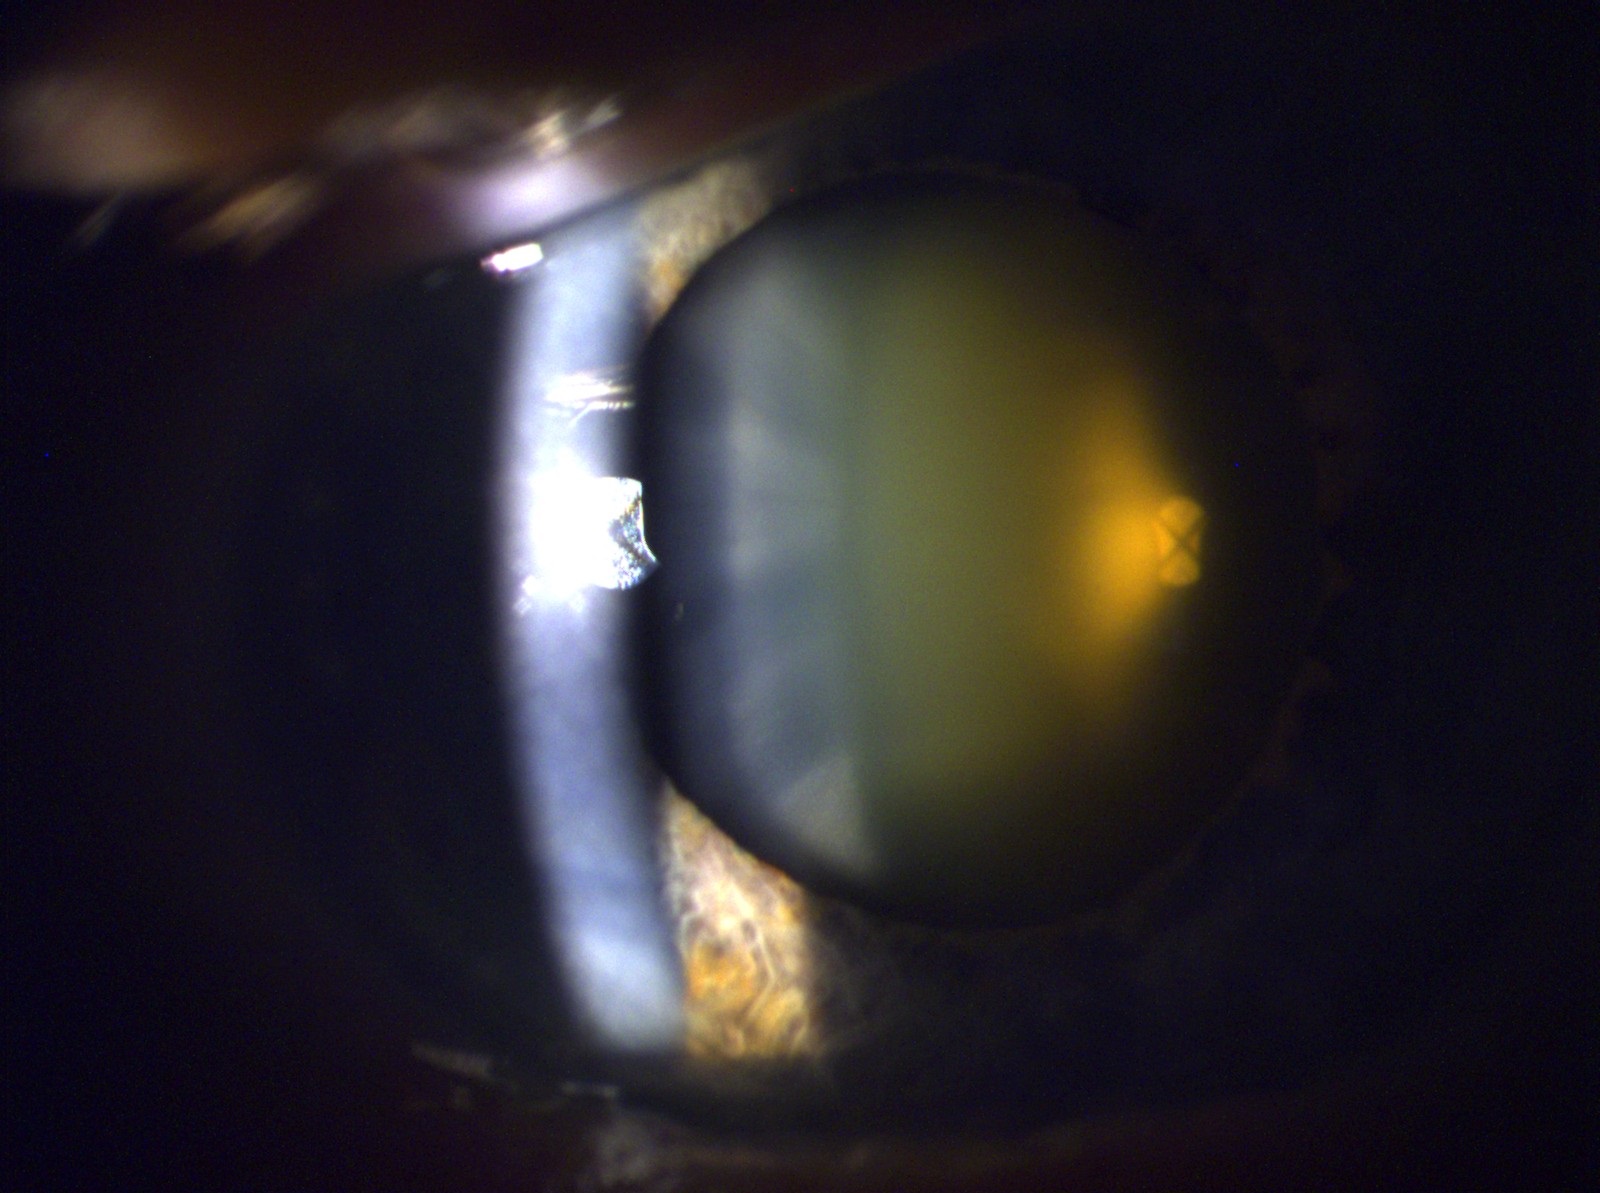

Grauer Star (Cataract)

- Beratung, Planung und Nachsorge bzgl. Cataract Operation

- Nachstarbehandlung mittels YAG-Laser-Kapsulotomie